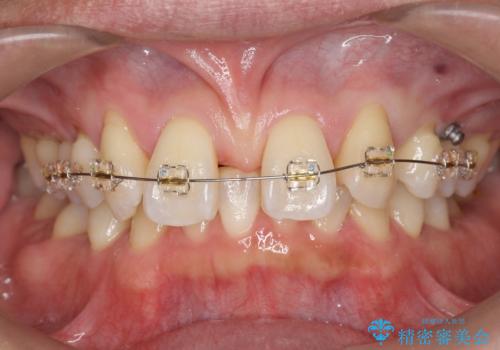

- 前歯部のすきっぱと歯並びが気になるので診て欲しいといらっしゃった方の症例です。

全顎矯正は御希望されなかったため、上顎前歯部のみの部分矯正とオールセラミッククラウンによる補綴を行いました。

今回用いたオールセラミッククラウンはジルコニアフレームという白い素材の上にセラミックを盛っているため、審美性が非常に高いのが特徴です。

また、ジルコニアは人工ダイヤモンドの材料にも使われているほど高い強度を持っており、そのためオールセラミッククラウンは審美性だけでなく、奥歯やブリッジの補綴も可能とするクラウンです。